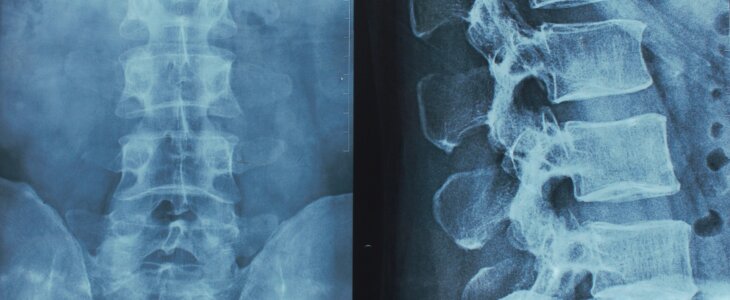

What Is a Herniated Disc?

Your spine is made up of bones called vertebrae, and between them are rubbery cushions called discs. When one of those discs tears or bulges out of place, it’s called a herniated disc. This can put painful pressure on nearby nerves, causing symptoms that radiate through your back, arms, or legs.

These injuries don’t always show up on X-rays and can be overlooked—until the pain becomes impossible to ignore. If you’ve been injured, it’s important to seek a thorough medical evaluation.

These include ER visits, imaging (like MRIs or CT scans), chiropractic care, physical therapy, spinal injections, and surgical procedures such as discectomy or spinal fusion.